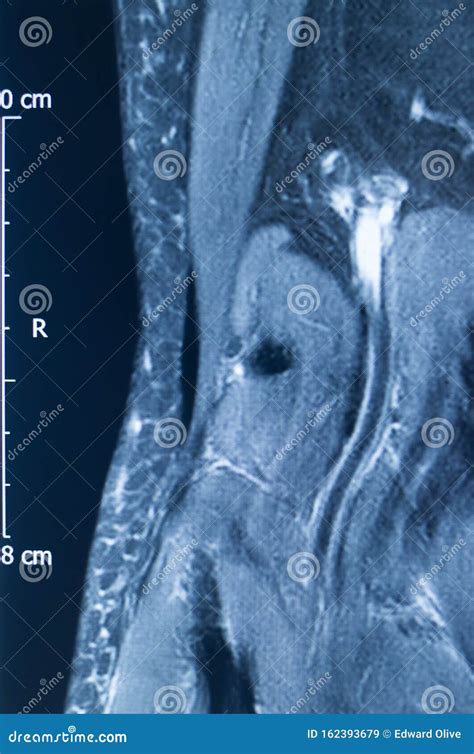

Diagnosing an MCL Tear with an MRI

An Mcl Tear Mri is a non-invasive imaging technique that provides detailed images of the knee joint. MRI uses magnetic fields and radio waves to create cross-sectional images of the body’s internal structures. This allows healthcare professionals to visualize the MCL and other soft tissues in the knee, identifying any tears or damage.

During an *Mcl Tear Mri*, the patient lies on a table that slides into a large, cylindrical machine. The procedure is painless and typically takes about 30-60 minutes. The MRI machine captures multiple images from different angles, providing a comprehensive view of the knee joint.

An *Mcl Tear Mri* can help determine the grade of the MCL tear, which is classified as follows:

An *Mcl Tear Mri* is particularly useful for differentiating between an MCL tear and other knee injuries, such as meniscal tears or anterior cruciate ligament (ACL) injuries. This information is crucial for developing an appropriate treatment plan.